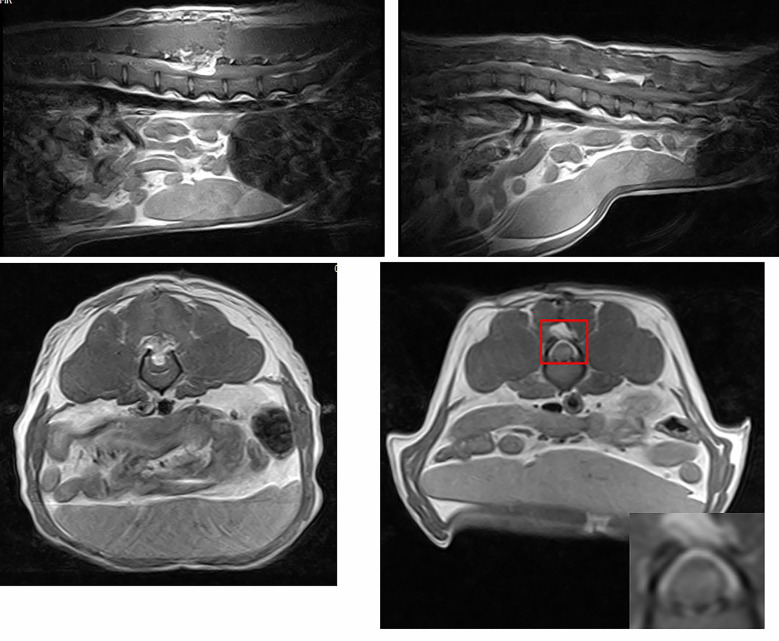

幹細胞治療病例

就診對象:

2 歲雄性比格犬,體重 9 公斤

就診原因:

因外傷造成腰椎 L3–L4 急性脊髓損傷,導致後肢無法站立、行動困難,伴隨感覺及運動功能喪失。

臨床檢查:

- 行為觀察:後肢完全癱瘓,無痛覺(Olby 評分 0 分)

- 影像檢查:MRI 顯示 L3–L4 節段脊髓受損,損傷區呈高信號

- 其他:血液與全身健康檢查正常,排除其他合併疾病

治療方式:

- 外科手術:L3–L4 節段脊髓減壓

- 幹細胞移植:

- 異體羊水來源間質幹細胞(AF-MSCs)5 × 10^6 個直接注射於損傷部位

- 手術同時完成,避免二次損傷

- 後續觀察與復健:

- 每週評估後肢運動功能

- MRI 隨訪脊髓結構變化

治療結果:

- 功能恢復:移植 4 週後,後肢運動明顯改善,步態接近正常

- 影像學變化:MRI 顯示受損脊髓區域軸突再髓鞘化

- 組織學與免疫組織化學:H&E 染色顯示灰白質分界清楚,神經標誌 nestin 與 β3-tubulin 表達,顯示神經細胞再生

- 長期觀察:犬因肺炎死亡,但脊髓組織仍顯示幹細胞治療效果

這隻狗因腰椎受傷導致後肢癱瘓,經手術減壓搭配幹細胞注射治療後,後肢運動功能明顯改善。MRI 和組織檢查都顯示神經組織有再生現象。這個案例顯示,幹細胞治療可能對脊髓損傷有幫助,但仍需配合手術及專業獸醫評估。